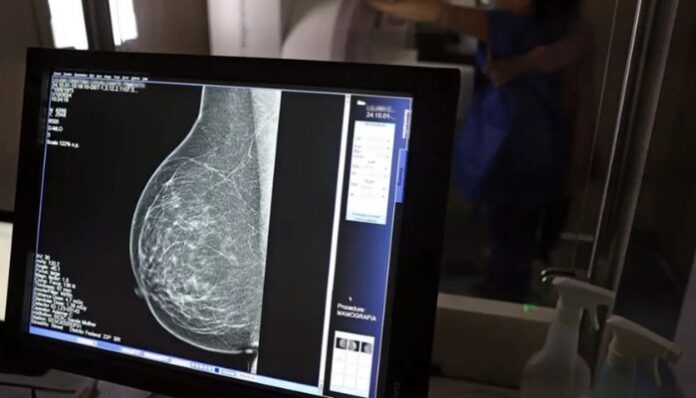

O Ministério da Saúde passou a recomendar o acesso a mamografia, via Sistema Único de Saúde (SUS), para mulheres de 40 a 49 anos – mesmo que não haja sinais ou sintomas de câncer de mama. De acordo com a pasta, a faixa etária concentra 23% dos casos da doença, e a detecção precoce aumenta as chances de cura.

Até então, a orientação era que o exame fosse feito a partir dos 50 anos.

As mamografias via SUS em pacientes com menos de 50 anos, de acordo com a pasta, representam 30% do total, o equivalente a mais de 1 milhão apenas no ano de 2024.

Os números mostram que, em 2024, cerca de 4 milhões de mamografias para rastreamento e 376,7 mil exames diagnósticos foram realizados no SUS.